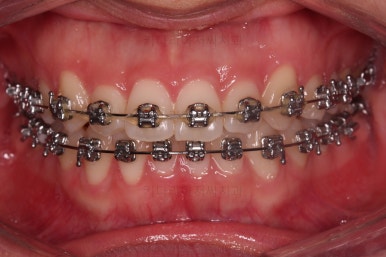

이번에 사용한 장치는 엠파워 메탈이라고 하는 자가결찰 금속 장치에요.

메탈이라고 모두 옛날방식의 장치가 아니랍니다.

"자가결찰"이냐 아니냐가 예전 장치와 요증 장치를 구분 짓는 기준이에요.

자가결찰이 아닌 세라믹이 자가결찰인 메탈보다 구세대 장치라는 거죠.

자가결찰이 여러모로 장점이 많고요.

다만, 재료에 따라 메탈도 있고 세라믹도 있어서 시각적인 차이가 있는거죠.

점점 가지런해지고 있네요.